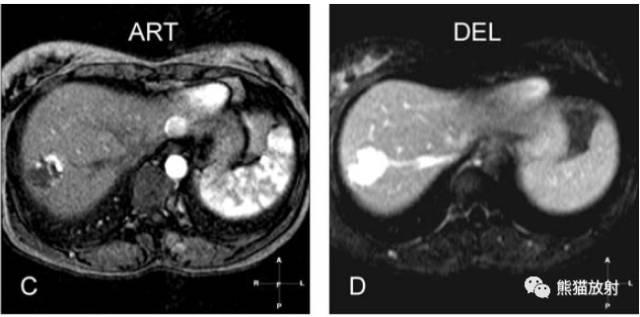

各序列信号特征:

T2 fatsat:T2压脂,明亮高信号;

T1 in-phase:T1同相位,低信号;

ART:动脉期,肿瘤大部分明显均匀强化(实心箭),周围可见轻微强化区(空心箭);

DEL:延迟期,血管瘤均匀持续强化。

A~D:影像表现如上所述。

E:黑血平面回波成像(流动敏感扩散梯度),血管瘤内局部信号缺失,提示高速血流;

F:反相位呈低信号;

G:动脉晚期,周围区域强化更加明显(空心箭);

H:门脉期,周围区域不再强化,肝脏信号均匀。